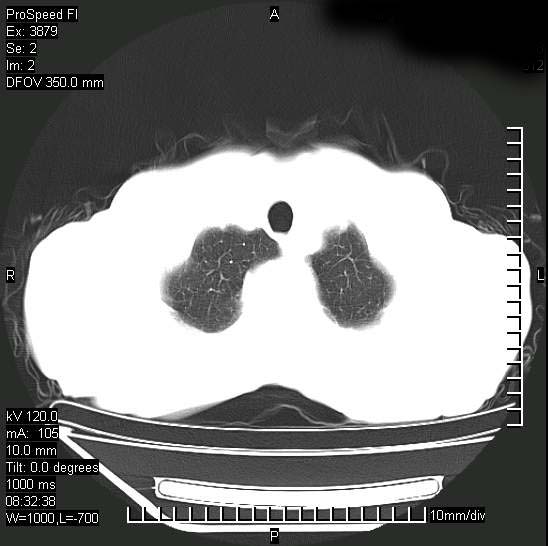

以下是引用37度在2008-6-6 11:20:00的发言:[br]1.包裹性积液,多考虑结核性;[br]2.穿刺术后改变。

以下是引用312nanyang在2008-6-6 15:12:00的发言:[br]基本支持楼主意见[br]疑问?左下肺支气管旁的软组织(16层)密度怎么解释?淋巴结还是斜裂胸膜增厚所致?能否增强进一步检查